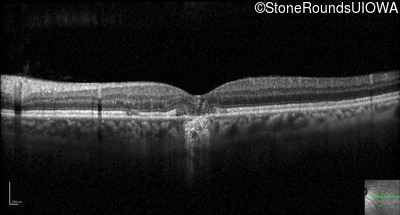

Optical Coherence Tomography - Left - 20/40 -2

Exemplar / OCT Stack